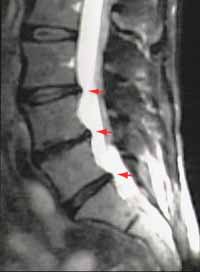

MRI

Prolaps auf der Höhe L4-L5

Contrairement au CT, l’IRM n’utilise pas de rayons x. On peut visualiser la colonne vertébrale en coupe sagittale et coronale. Es ist vor allem in der Darstellung des Nervensystems und der Weichteile, also gerade der Bandscheiben und der Nervenwurzeln, dem CT überlegen. |

Des hernies discales à plusieurs niveaux ont pu être observées chez de nombreuses personnes totalement asymptomatiques.

Sur cette IRM on peut voir trois hernies discales à trois niveaux différents. |